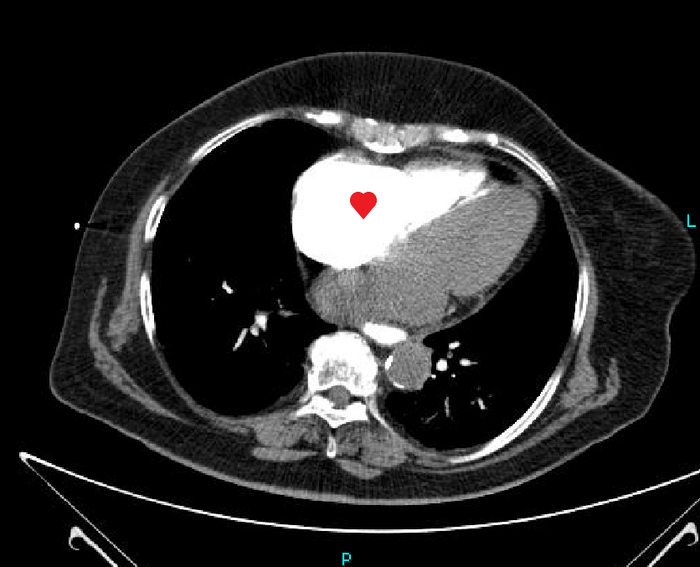

Пациент, 79 лет, направлен коллегой-терапевтом на компьютерную томографию органов градной клетки с жалобами на хронический кашель с мокротой. В анамнезе ожирение, сахарный диабет, стенокардия.

По КТ в мягкотканном окне (специальные настройки яркости и контраста для лучшего отображения мягких тканей) определялись увеличенные лимфатические узлы в средостении справа паратрахеально, в области корня правого лёгкого и инфракаринально (ниже места "разделения" трахеи на правый и левый бронх):